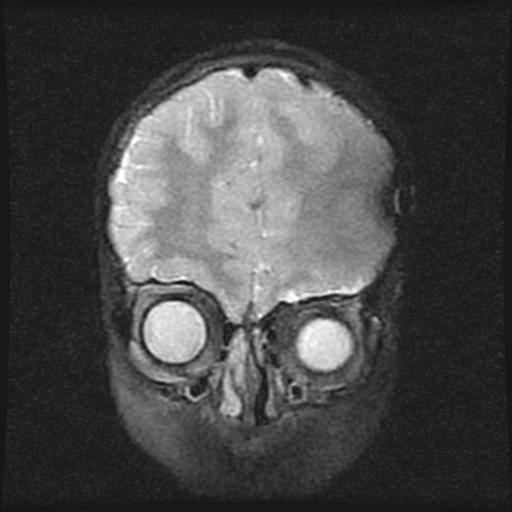

标题: PED0377: 6岁小儿,左侧视神经瘤术后 [打印本页]

标题: PED0377: 6岁小儿,左侧视神经瘤术后

6岁小儿,左侧视神经瘤术后。现左侧视力减退。